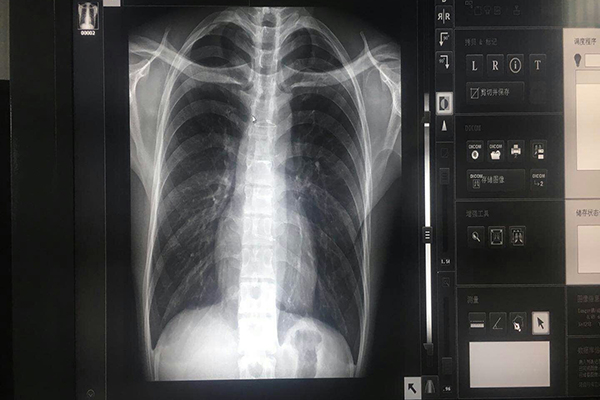

醫(yī)療灰階監(jiān)視器能夠通過專用的校正儀和校正軟件對顯示器的輸入和輸出進(jìn)行曲線校正,使之符合DICOM曲線。用顯示器有:10 bit-1024灰階,用于顯示X光灰階圖象,與診斷相關(guān),要求:10bit11bit(1024*2048灰階)。支持BBS功能(穩(wěn)定的亮度控制)。